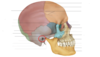

Reconozca la marca ósea encerrada en el círculo

Meato acústico externo

Conducto auditivo externo